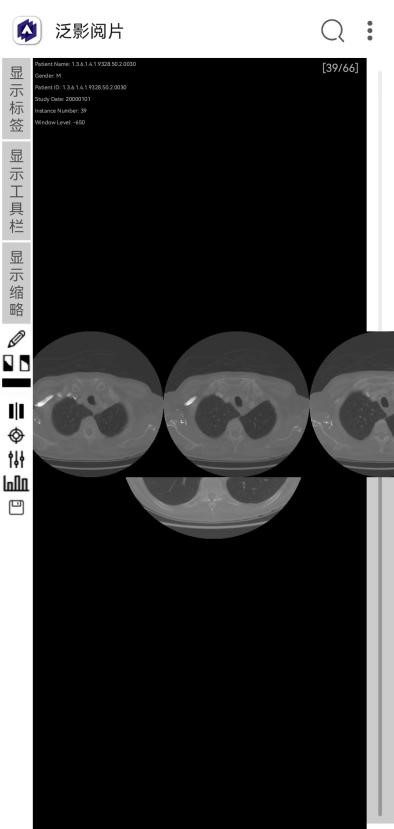

打开图像序列,即打开指定文件夹下的图像序列,打开后可用右侧导航栏翻阅序列,如下图所示。

显示缩略图。打开序列后可以列表方式显示序列的缩略图,方便浏览查看,如下图所示。